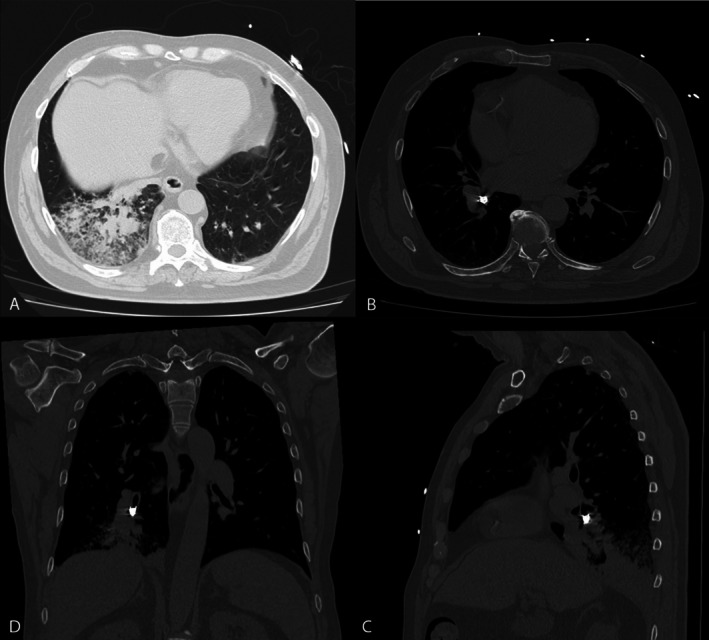

A Crumpet, a Canine and a Cryoprobe: A Case of Tooth Aspiration.

Foreign body inhalation can lead to post-obstructive pneumonia and sepsis, requiring timely removal to achieve source control. We report a case of tooth aspiration successfully retrieved with a cryoprobe.